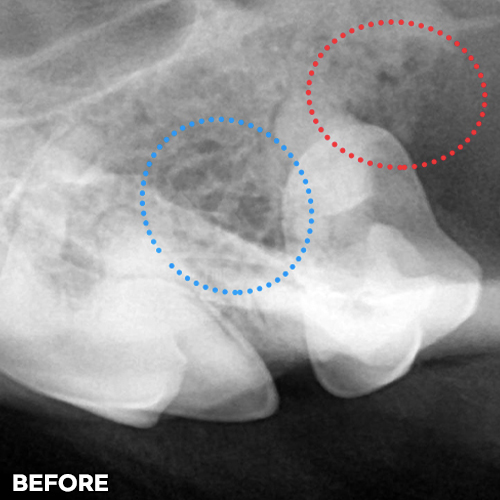

[강아지잇몸뼈 치료 후 2달 경과]

[강아지잇몸뼈 재생치료 하고 재생된 자기 잇몸뼈]